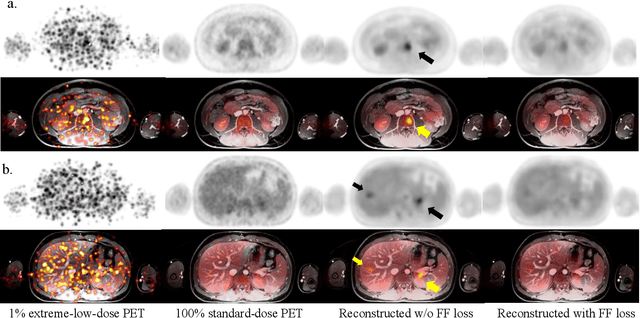

Abstract:Despite its tremendous value for the diagnosis, treatment monitoring and surveillance of children with cancer, whole body staging with positron emission tomography (PET) is time consuming and associated with considerable radiation exposure. 100x (1% of the standard clinical dosage) ultra-low-dose/ultra-fast whole-body PET reconstruction has the potential for cancer imaging with unprecedented speed and improved safety, but it cannot be achieved by the naive use of machine learning techniques. In this study, we utilize the global similarity between baseline and follow-up PET and magnetic resonance (MR) images to develop Masked-LMCTrans, a longitudinal multi-modality co-attentional CNN-Transformer that provides interaction and joint reasoning between serial PET/MRs of the same patient. We mask the tumor area in the referenced baseline PET and reconstruct the follow-up PET scans. In this manner, Masked-LMCTrans reconstructs 100x almost-zero radio-exposure whole-body PET that was not possible before. The technique also opens a new pathway for longitudinal radiology imaging reconstruction, a significantly under-explored area to date. Our model was trained and tested with Stanford PET/MRI scans of pediatric lymphoma patients and evaluated externally on PET/MRI images from T\"ubingen University. The high image quality of the reconstructed 100x whole-body PET images resulting from the application of Masked-LMCTrans will substantially advance the development of safer imaging approaches and shorter exam-durations for pediatric patients, as well as expand the possibilities for frequent longitudinal monitoring of these patients by PET.